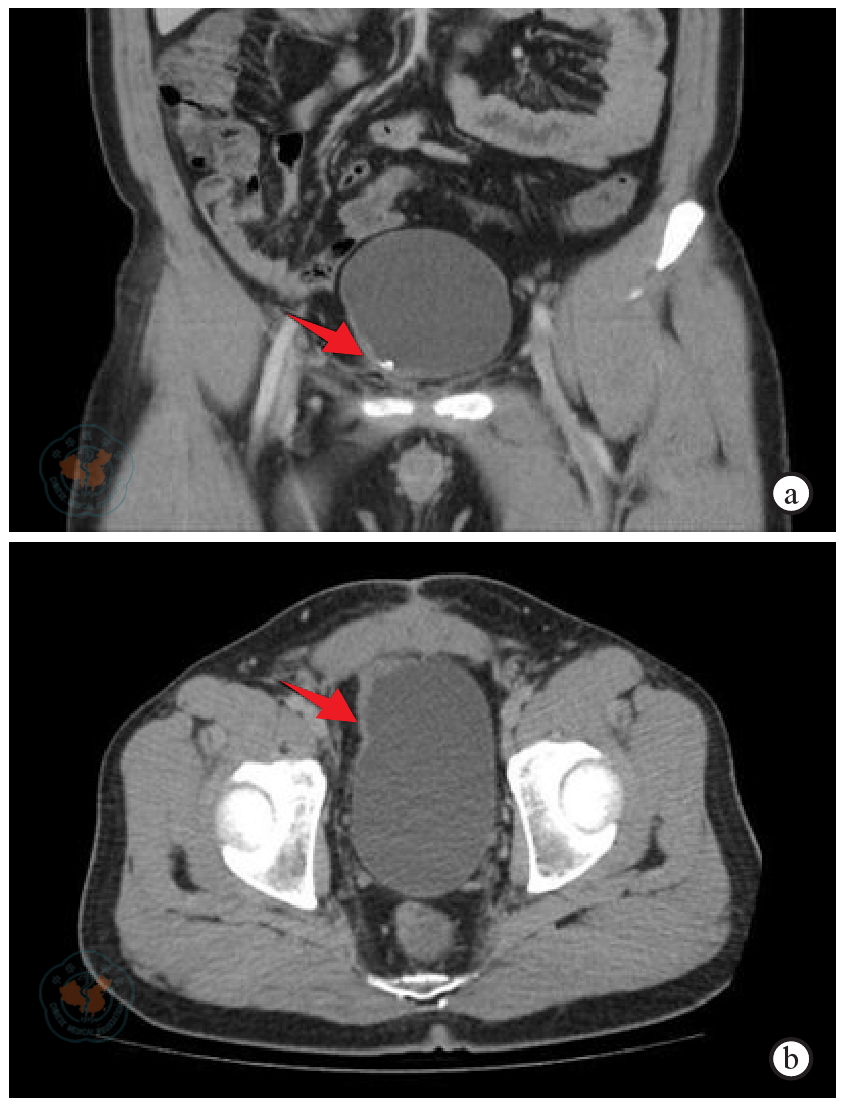

图4 膀胱低级别平滑肌肉瘤患者术后1年和2年盆腔影像注:a~b为患者术后1年盆腔MRI示未见肿瘤复发,c~d为患者术后2年盆腔CT示大致同前,建议随诊